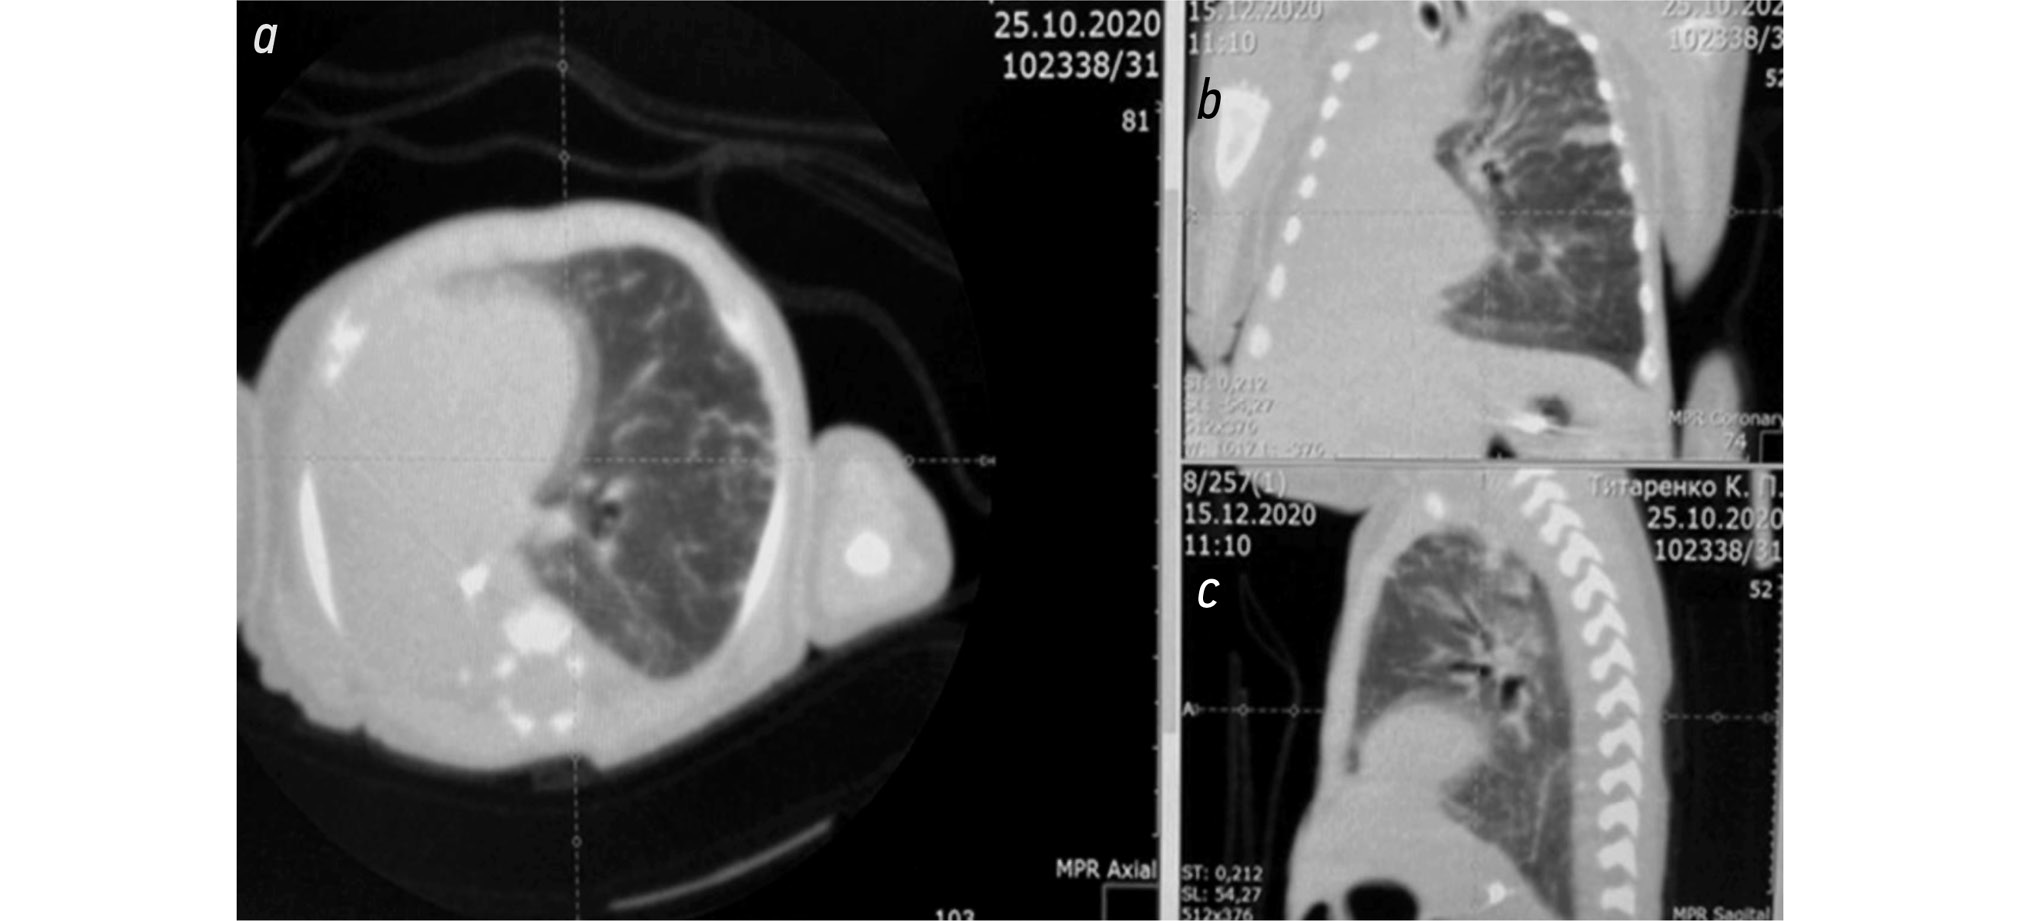

С целью исключения врождённых пороков развития лёгких — подковообразное лёгкое, трахеобронхомаляция, лобарная эмфизема, гипоплазия лёгкого, бронхогенная киста, объёмное образование в грудной полости — в возрасте 1,5 мес. была выполнена мультиспиральная компьютерная томография-ангиография (МСКТА) органов грудной полости (рис. 6).

Рис. 6. Мультиспиральная компьютерная томография-ангиография органов грудной полости на 1,5 мес. жизни: тотальный ателектаз правого лёгкого (a — аксиальная реконструкция, b — фронтальная реконструкция; c — сагиттальная реконструкция).

Fig. 6. Multispiral computed tomography-angiography of the chest organs at 1.5 months of life: total atelectasis of the right lung (a — axial reconstruction, b — frontal reconstruction; c — sagittal reconstruction).

Выявлена картина ТАПЛ с компенсаторным вздутием ткани левого лёгкого и формированием передней парамедиастинальной грыжи. Органы средостения резко смещены вправо. Обнаружены признаки дистонии трахеи, а также деформация и обструкция устьев обоих главных бронхов, более выраженная справа. Другие возможные причины хронического ателектаза правого лёгкого — гипоплазия правой лёгочной артерии, нарушение васкуляризации лёгочной ткани правого лёгкого — не обнаружены.